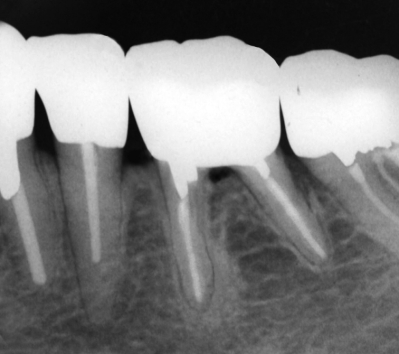

63歳の女性。口臭を主訴として来院した。1か月前から左側の下顎臼歯部に嫌な臭いを感じるようになったという。口腔清掃状態は良好で、下顎臼歯部に自発痛や咬合痛は認めない。歯周ポケットは2mm以下であるが、下顎左側第一大臼歯の分岐部はポケット探針が貫通する。再修復を行うこととした。初診時、前処置後のポストコア合着時および補綴装置装着後の口腔内写真と、初診時のエックス線写真を別に示す。